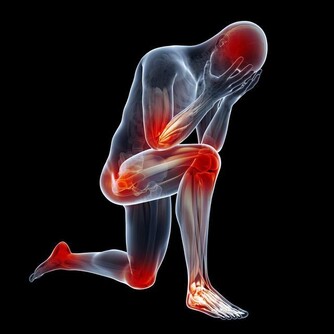

若不注意腳踝的保暖,在濕冷天氣里,很容易引發關節炎等風濕疾病。

露腳踝易得踝關節炎現在很多年輕人把捲起褲腿或者穿短襪露出白皙纖細的腳腕當成一種時尚。但在醫生看來,這種看似時尚的穿著,最容易誘發踝關節炎。

東南大學附屬中大醫院中醫骨傷科主任屈留新解釋,腳踝部位分布著淋巴管、血管、神經等近十個重要的組織,被稱為人體的第二心臟,如果經常把腳踝露出來,不僅會引發踝關節炎,還會使抗病能力下降而導致感冒。

另外,東南大學附屬中大醫院中醫骨科副主任醫師陸軍說,腳踝承受著全身的重量,是人體比較脆弱的地方,對外傷缺乏緩衝,很容易受到各種傷害。再加上踝關節周圍軟組織少,局部血液循環較差,如果再不穿襪子加以保護,很容易著涼而引發疾病。而能不能露腳踝,還要看個人體質,不要盲目去效仿。

膝關節:預防老寒腿很多年輕女性喜歡短裙,膝關節長期暴露在寒冷的環境中,會引起血液循環不通暢,導致老寒腿,出現腿部酸麻脹痛而且還有沉重感。